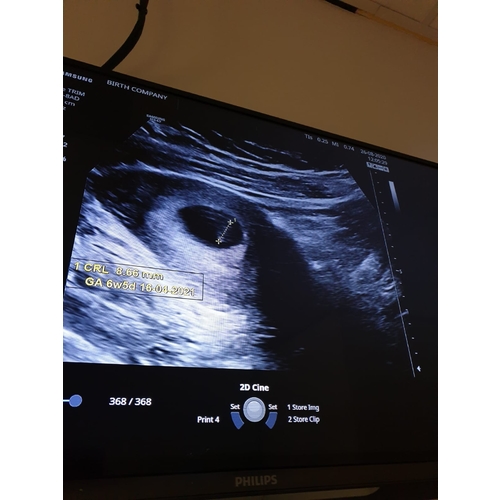

Maar verloskundige denkt gwn dat ik 7 weken ben maar het was lastig om het goed op de echo te zien hier staat ook hoeveel mm of cm het is

Kleintje was 7,8mm ongeveer. Ze dacht bijna 7 weken. Heb over 2,t week weer een afspraak